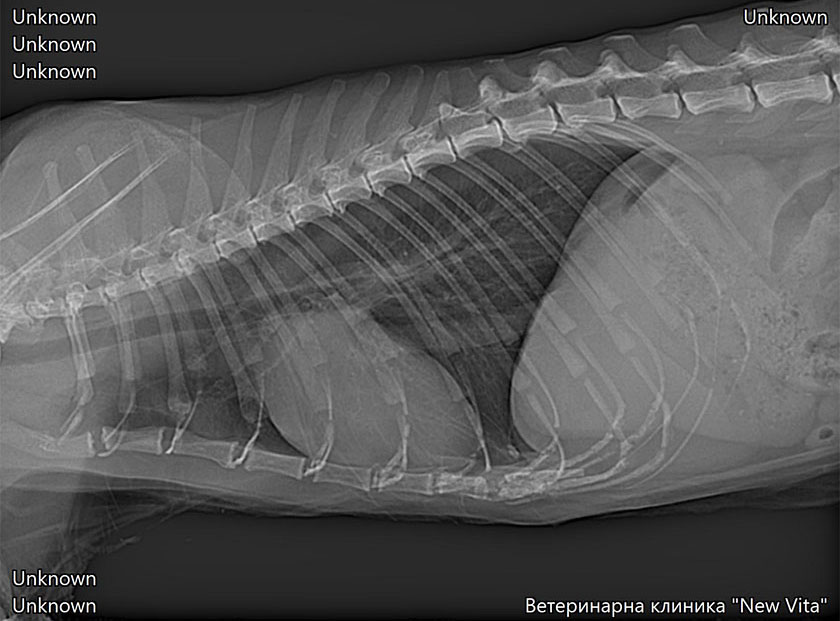

Най-честата рентгенологична находка при котки със сърдечни проблеми е наличието на плеврален излив, оток на белия дроб, Увеличени белодробни съдове, увеличен сърдечен силует-кардиомегалия (не е задължително да се установи, за да бъде поставена диагнозата, много често сърцето е външни размери). Процедурата по получаване на качествени и диагностични рентгенологични снимки може да бъде отложена докато пациента не бъде стабилизиран. Изискват се минимум две рентгенови снимки в две проекции.

Това са рентгенови снимки на наши пациенти. Те показват наличие на плеврален излив и оток на белия дроб.